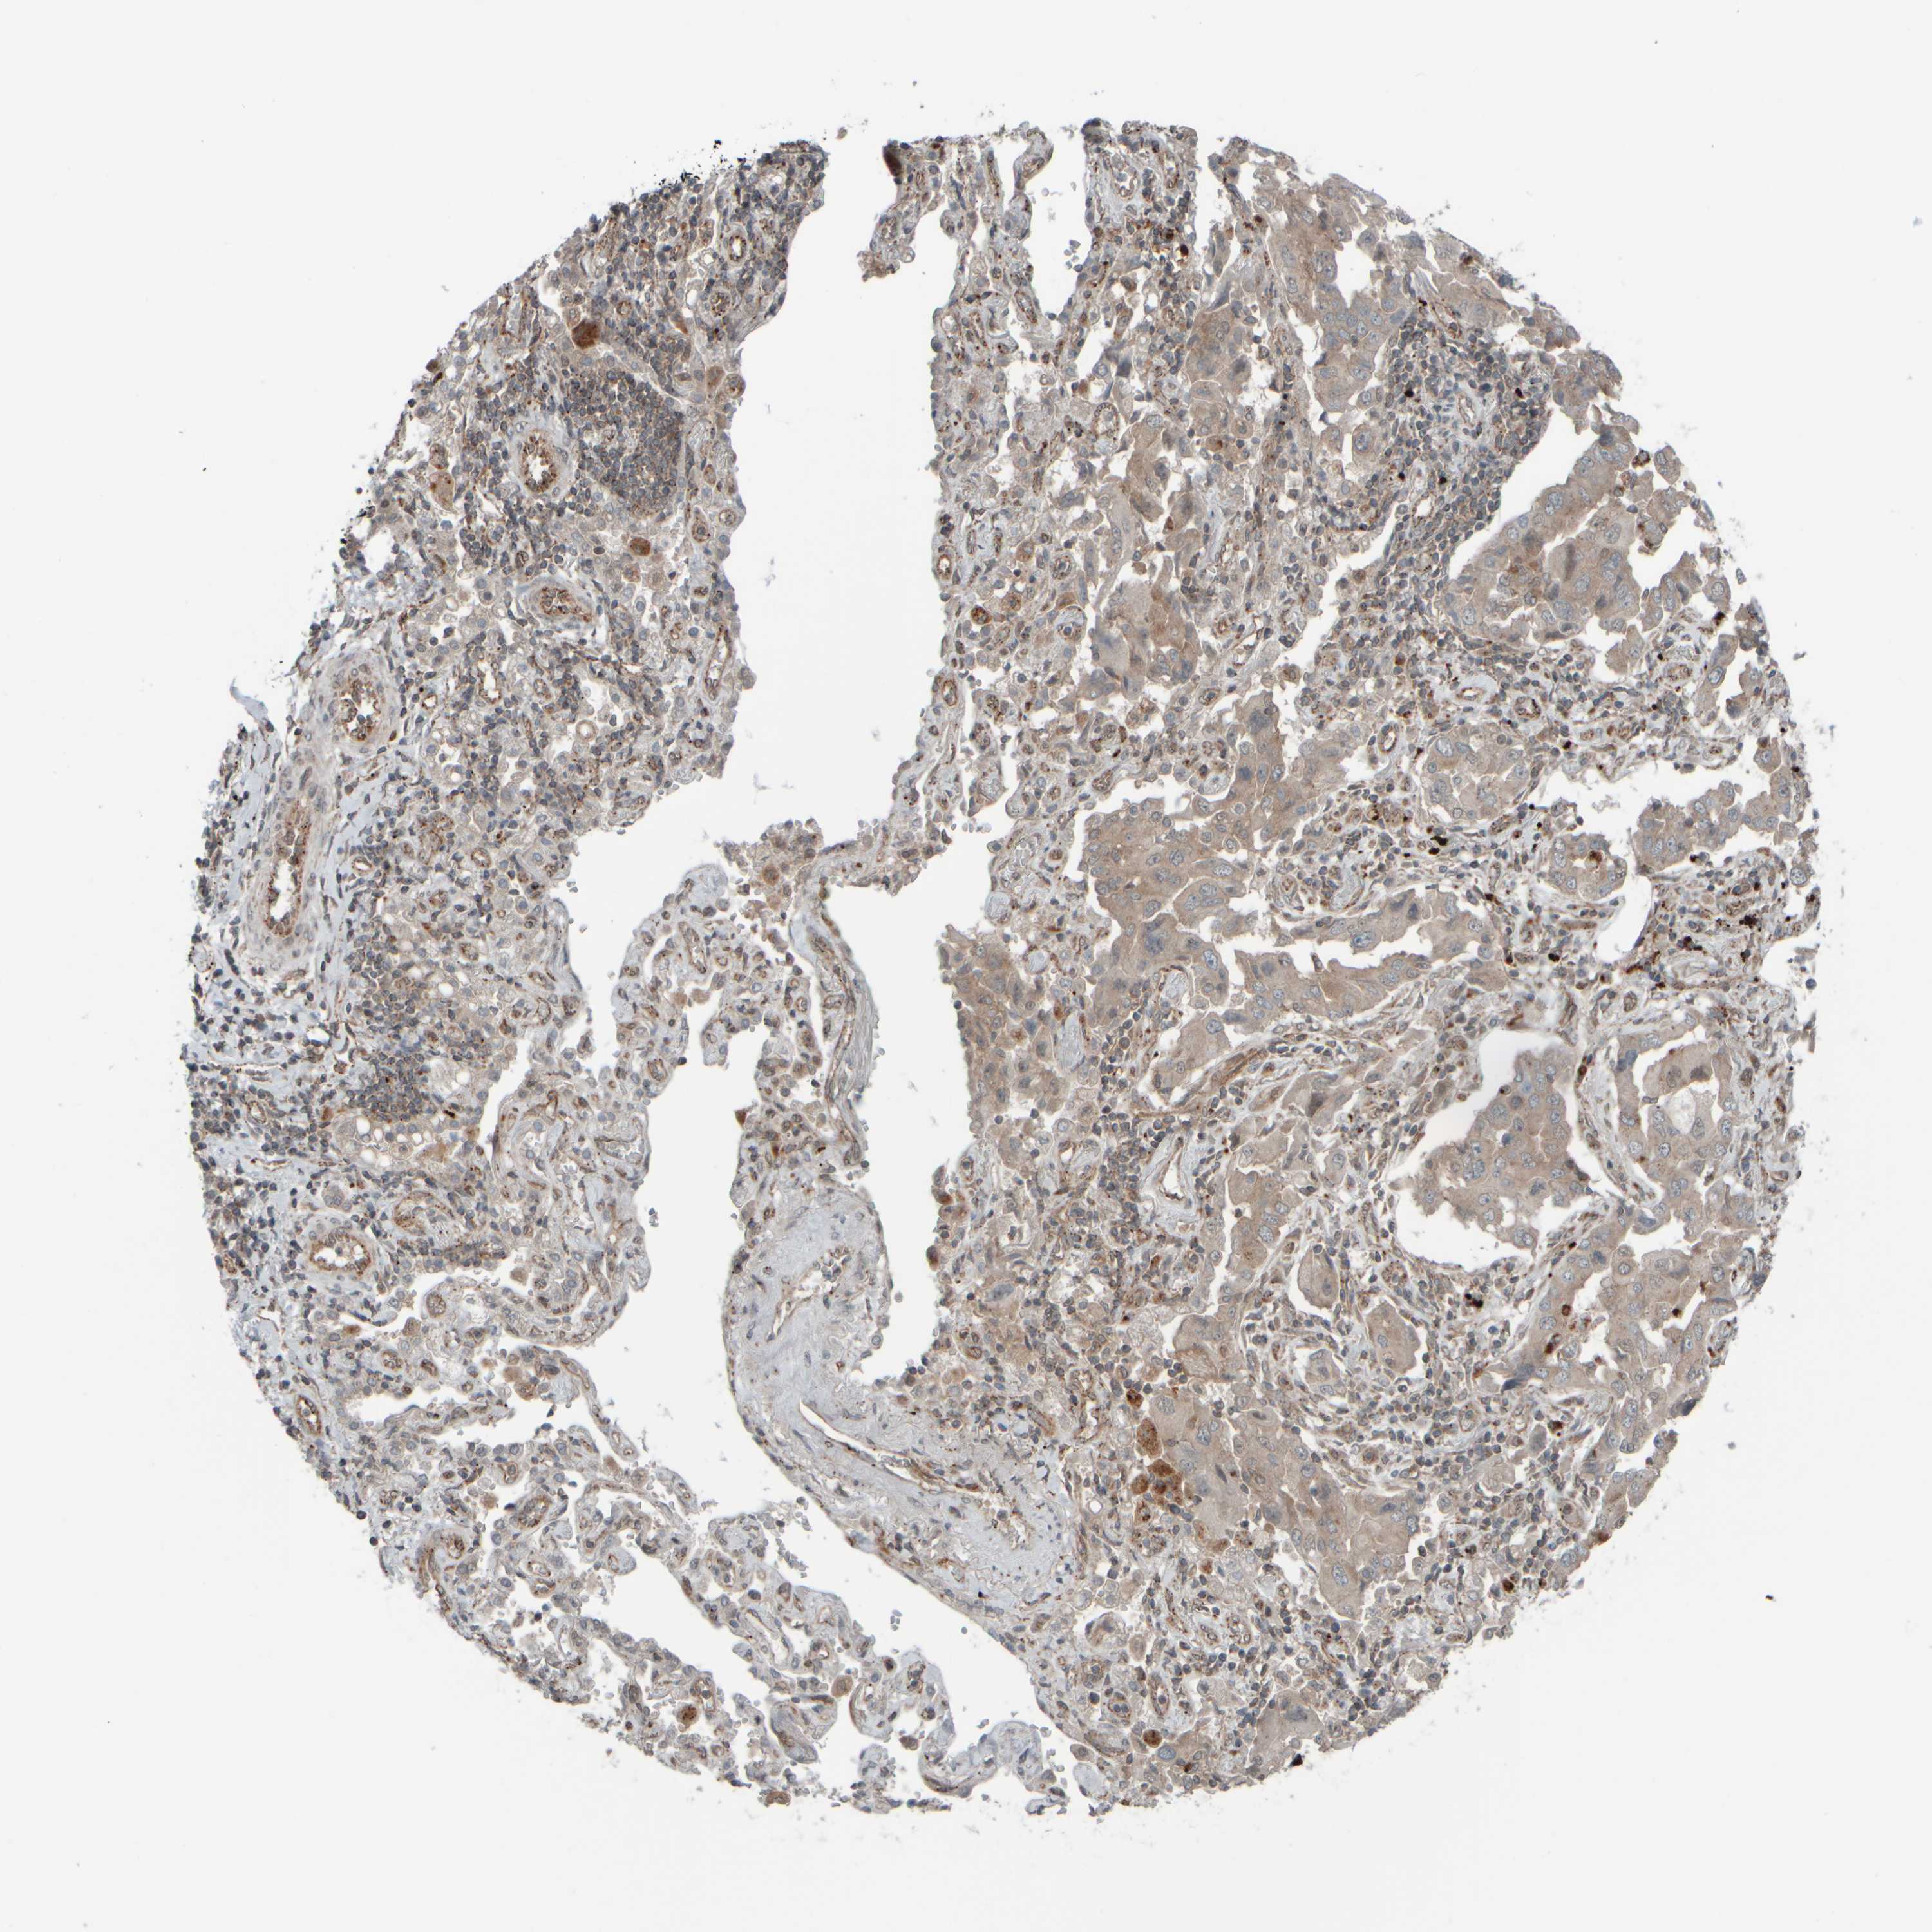

LUNG ADENOCARCINOMA (VALIDATION) - Interactive survival scatter ploti

The Survival Scatter plot shows the clinical status (i.e. dead or alive) for all individuals in the patient cohort, based on the same data that underlies the corresponding Kaplan-Meier plots. Patients that are alive at last time for follow-up are shown in blue and patients who have died during the study are shown in red.

The x-axis shows the expression levels (FPKM) of the investigated gene in the tumor tissue at the time of diagnosis. The y-axis shows the follow-up time after diagnosis (years). Both axes are complimented with kernel density curves demonstrating the data density over the axes. The top density plot shows the expression levels (FPKM) distribution among dead (red) and alive patients (blue). The right density plot shows the data density of the survived years of dead patients with high and low expression levels respectively, stratified using the cutoff indicated by the vertical dashed line through the Survival Scatter plot. This cutoff is automatically defined based on the FPKM cutoff that minimizes the p-score. The cutoff can be changed by dragging the vertical line or by entering a cutoff value in the square labeled "Current cut-off".

Under the Survival Scatter plot the p-score landscape (black curve; left axis) is shown together with dead median separation (red curve; right axis). Dead median separation is the difference in median mRNA expression between patients who have died with high and low expression, respectively. It is calculated as follows: median FPKM expression of dead patients with high expression - median FPKM expression of dead patients with low expression. This is intended to aid the user in visually exploring custom cutoffs and the associated p-scores and dead median separation.

Individual patient data is displayed and can be filtered by clicking on one or more of the category buttons on the top of the page. Categories describing expression level and patient information include: high, low, alive, dead, female, male and tumor stages. The scale of the x-axis can be toggled between linear and log-scale by clicking on the "x log" button. Mouse-over function shows TCGA ID, patient information and mRNA expression (FPKM) for each patient.

& Survival analysisi

Kaplan-Meier plots summarize results from analysis of correlation between mRNA expression level and patient survival. Patients were divided based on level of expression into one of the two groups "low" (under cut off) or "high" (over cut off). X-axis shows time for survival (years) and y-axis shows the probability of survival, where 1.0 corresponds to 100 percent.

GIGYF1 is not prognostic in Lung Adenocarcinoma (validation)

: 15.23

Average pTPM 13.0

Number of samples 105